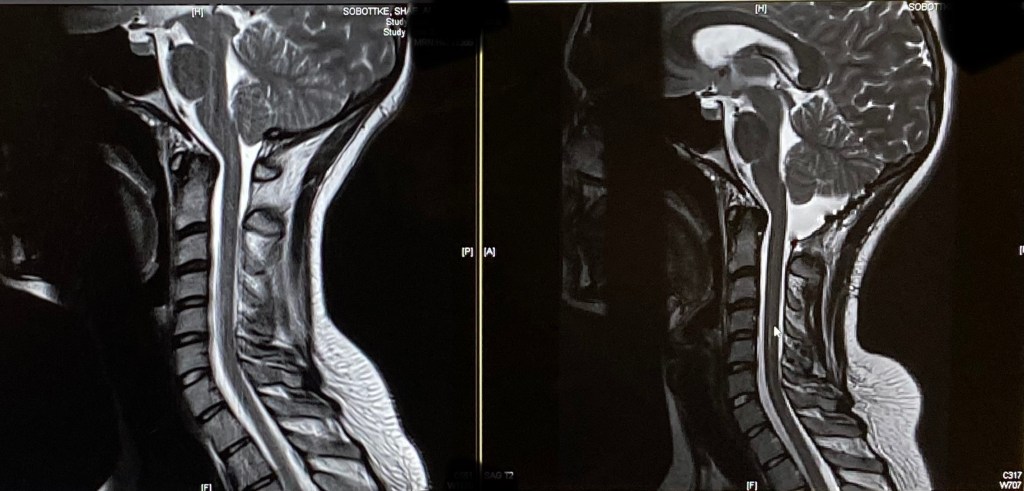

So, I was readmitted a scans showed a Seroma (fluid collection at the surgery site) that the ER was concerned about. The surgeon later told me that it’s very common and they would be surprised not to have one. That the ER always makes a big deal out of it.